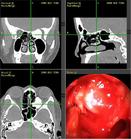

局部檢查可見覆有正常黏膜的光滑硬性腫塊,常並發息肉和鼻竇炎。X線攝片有助於鼻骨瘤的診斷,可以判定其性質、部位、範圍及附著處等。手術探查及術後活檢可得確診。